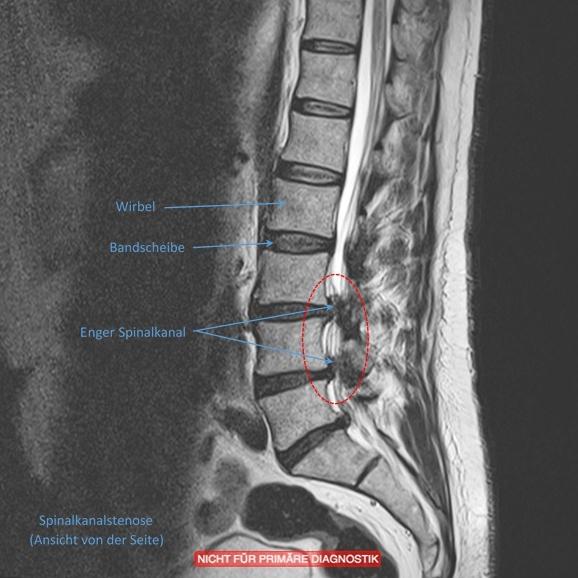

Spinalkanalstenose Lws Operation Erfahrungen . Spinalkanalstenose Foraminalstenose Operation Lendenwirbelsäule Zwischenwirbellöcher Die Klinik ist auch nach meinem zweiten Aufenthalt dort (vorher Hüfte) sehr empfehlenswert. Die OP (Spinalkanalstenose) erwies sich als voller Erfolg: die Schmerzen verschwanden wie durch ein Wunder über Nacht

Source: hsawaconaq.pages.dev Spinalkanalstenose • Symptome & Therapien , Spinalkanalstenose ,nun doch OP Dieses Thema im Forum "OP/Chirurgie, Synoviorthese, Gelenkpunktion usw." wurde erstellt von delphin, 17 Erfolgreiche OP an der Wirbelsäule (Spinalkanalstenose), meine starken Schmerzen sind 100% weg